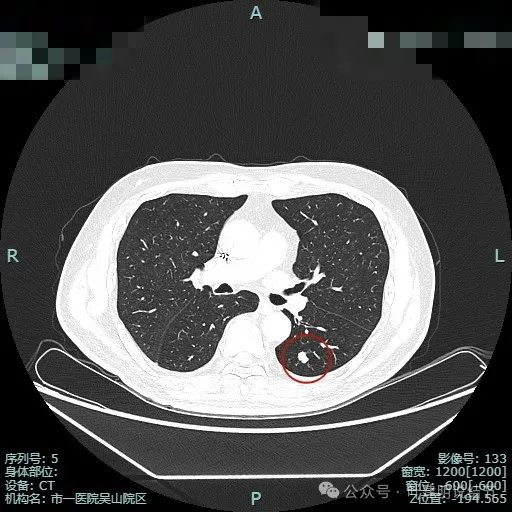

先看薄层平扫不同结节的情况:

左下叶背段主病灶,密度高,是实性的,表面不平,有点像土豆。

左下基底段实性结节,表面较平直,缺乏膨胀性,此灶2019年时就有存在,对比无显著变化。